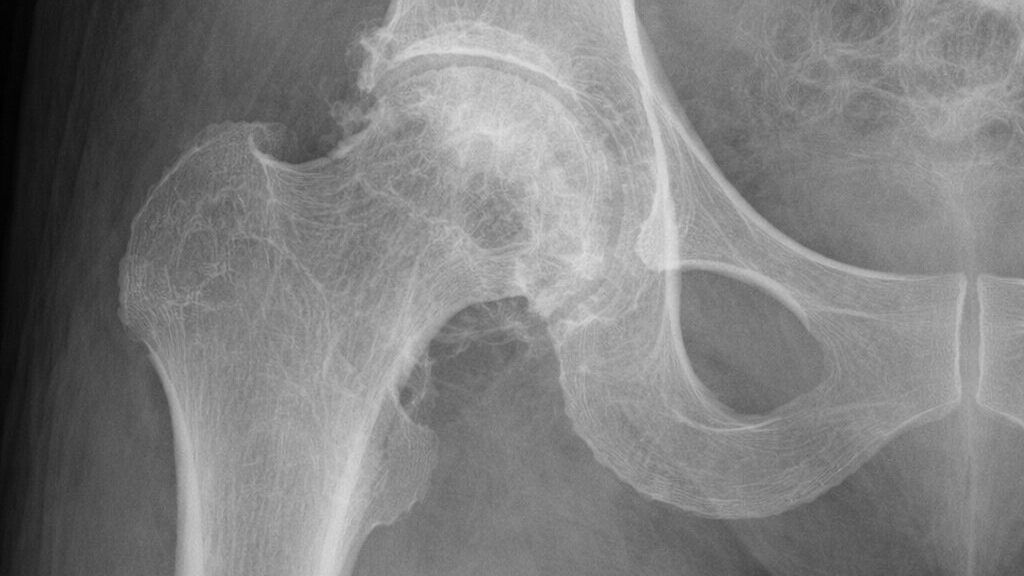

Deepfakes više nisu samo problem izbora ili društvenih mreža. Prema izvještaju STAT News, istraživači potvrđuju da deepfake medicinske snimke mogu zavesti i radiologe. To otvara sasvim novi front u sigurnosti zdravstvenog sustava – i dolazi s mjesta s kojeg ga nitko nije očekivao.

Do sada se priča o deepfakeovima vrtjela oko politike i zabave. Lažni videozapisi političara, manipulirane slike slavnih, sve je to već postalo dio medijskog krajolika. Ali kad lažna rendgenska snimka uđe u klinički sustav, posljedice su drugačije. Rani signali sugeriraju da čak i obučeni radiolozi ne prepoznaju manipulirane snimke. Hype oko AI u medicini dosad je bio optimističan – algoritmi kao pomoć, kao ubrzanje, kao drugi par očiju. Nitko nije računao na AI kao aktivnog protivnika.

Prema dostupnim informacijama, istraživači su uspjeli generirati deepfake X-ray snimke koje prolaze stručnu provjeru. No – i ovo je važno – ne znamo koliko je ova prijetnja raširena u stvarnom kliničkom okruženju. Podaci o prevalenciji jednostavno ne postoje. To stvara zanimljivu prazninu: sigurnosni alati za detekciju deepfakeova u medicini tek se razvijaju, dok je tehnologija za njihovo stvaranje već dostupna.